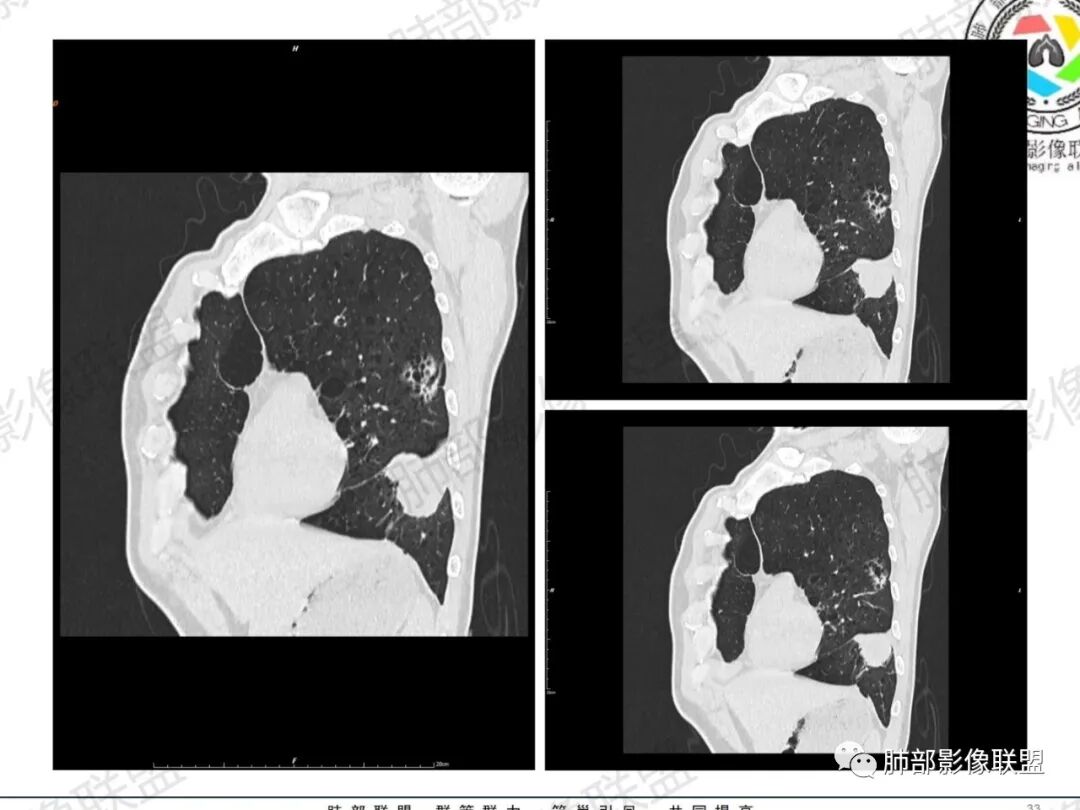

琦遇:恶性没有问题,肺气肿底子、病灶分叶、少许毛刺、叶间胸膜凹陷、部分边缘可见清晰的GGO、胸膜牵拉凹陷、局部胸水、近端支气管截断、部分支气管被推移、占位效应明显、强化特点为不均匀强化、内部有少许沼泽样低强化区,强化部分轻中强化为主、余肺可见转移性结节、左肺上叶似为囊腔型腺癌一枚,肿瘤标志物提示非小、神经内分泌,综合分析考虑大神泌、腺癌、腺鳞癌、鳞癌  同时左肺上叶囊腔型腺癌  肺转移

蕊:中老年男性,吸烟史,肺气肿背景,左肺上叶类圆形肿块影,边界清晰,边缘凹凸不平,有分叶,支气管进入阻断,临近胸膜栽赃,整体病灶膨隆,局部周围可以清晰ggo,临近叶间裂内凹,轻度强化,并可见多个低密度区,坏死可能,界线不清;肺内多结节,边缘光滑,考虑恶性伴转移,鳞癌、腺癌

傅昌瑜:中老年男性,肺气肿背景,右胸背疼痛1周。CEA、NSE、CYFRA—211升高。左上肺混合磨玻璃结节,内见较多空泡和扩张支气管。左下肺胸膜下肿块,边缘较光滑,深分叶,似有血管进入,与支气管关系不清,内见不均匀强化,见沼泽地样坏死,有胸膜栽赃。另两肺多发圆形小结节。考虑恶性并肺内转移,多原发可能性大,左上肺腺癌,左下肺病理难以判断,小细胞癌?鳞癌?

小锁:中老年男性,肺气肿背景,右胸背疼痛1周。CEA、NSE、CYFRA—211升高。左上肺混合磨玻璃结节,边界清楚,内见较多空泡。左下肺肿块,边缘清楚,深分叶,有血管和支气管进入,胸膜凹陷。另两肺多发圆形小结节。考虑双发原位癌,左上肺腺癌,左下肺大神泌或腺鳞癌可能,肺内转移。

蓝天白云:中年男性,肺气肿背景,左肺下叶肿块,边缘膨隆,有分叶,内有湖泊样坏死,有轻中度强化,局部胸膜栽赃,收缩力不强,周围见肺气肿征象。左肺上叶混合磨玻璃影,边界清楚,考虑都是恶性,左上肺iac,左下肺腺鳞癌,或大细胞肺癌可能。两肺多发结节,考虑转移

周太狼:中年男性,吸烟、高血压史,肿瘤指标升高,肺气肿背景下,左肺下叶肿块影,分叶、膨隆、未跨叶裂,支气管截断,不均匀强化。另双肺多发结节及磨玻璃影,左肺上叶混合磨玻璃,内可见多发空泡影。整体考虑恶性,肺癌伴肺内转移,左下肺鳞癌?神经内分泌癌?左肺上叶囊腔腺癌?

LCNEC最常见的影像特征包括:(1)肿块发生部位:周围型肺癌为主,少数发生于肺中央。(2)肿块大小及形态。因肿瘤细胞生长迅速常形成较大肿块,因此其体积一般较大,直径常在3~10cm范围内,病灶常为不规则形软组织肿块。(3)肿块边界。多数学者报道大多数肿块边界清晰,边缘呈分叶状,毛刺征及“胸膜凹陷征”少见,认为与该病对周围组织浸润较轻及较少产生纤维瘢痕组织牵拉有关联。(4)肿块密度、强化特点及代谢情况。据文献报道,该类肿瘤因体积较大CT上常见软组织肿块,且多数密度不均匀,内见囊变坏死区,增强后呈轻或中度不均匀强化(可见强化者占75.7%),认为其强化特点与其内部肉眼可见坏死灶和肿瘤较大直径有关。(5)伴随症状及远处转移。该病恶性程度高,侵袭性强,常侵犯邻近结构,如胸膜、心包、邻近骨质或纵隔内组织等,易出现纵隔淋巴结转移,部分发生肺内及远处转移,少数早期可出现广泛远处转移。